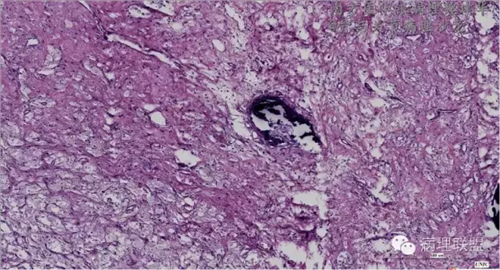

来源于组织细胞的相似性骨病ECD vs RDD 看图说话